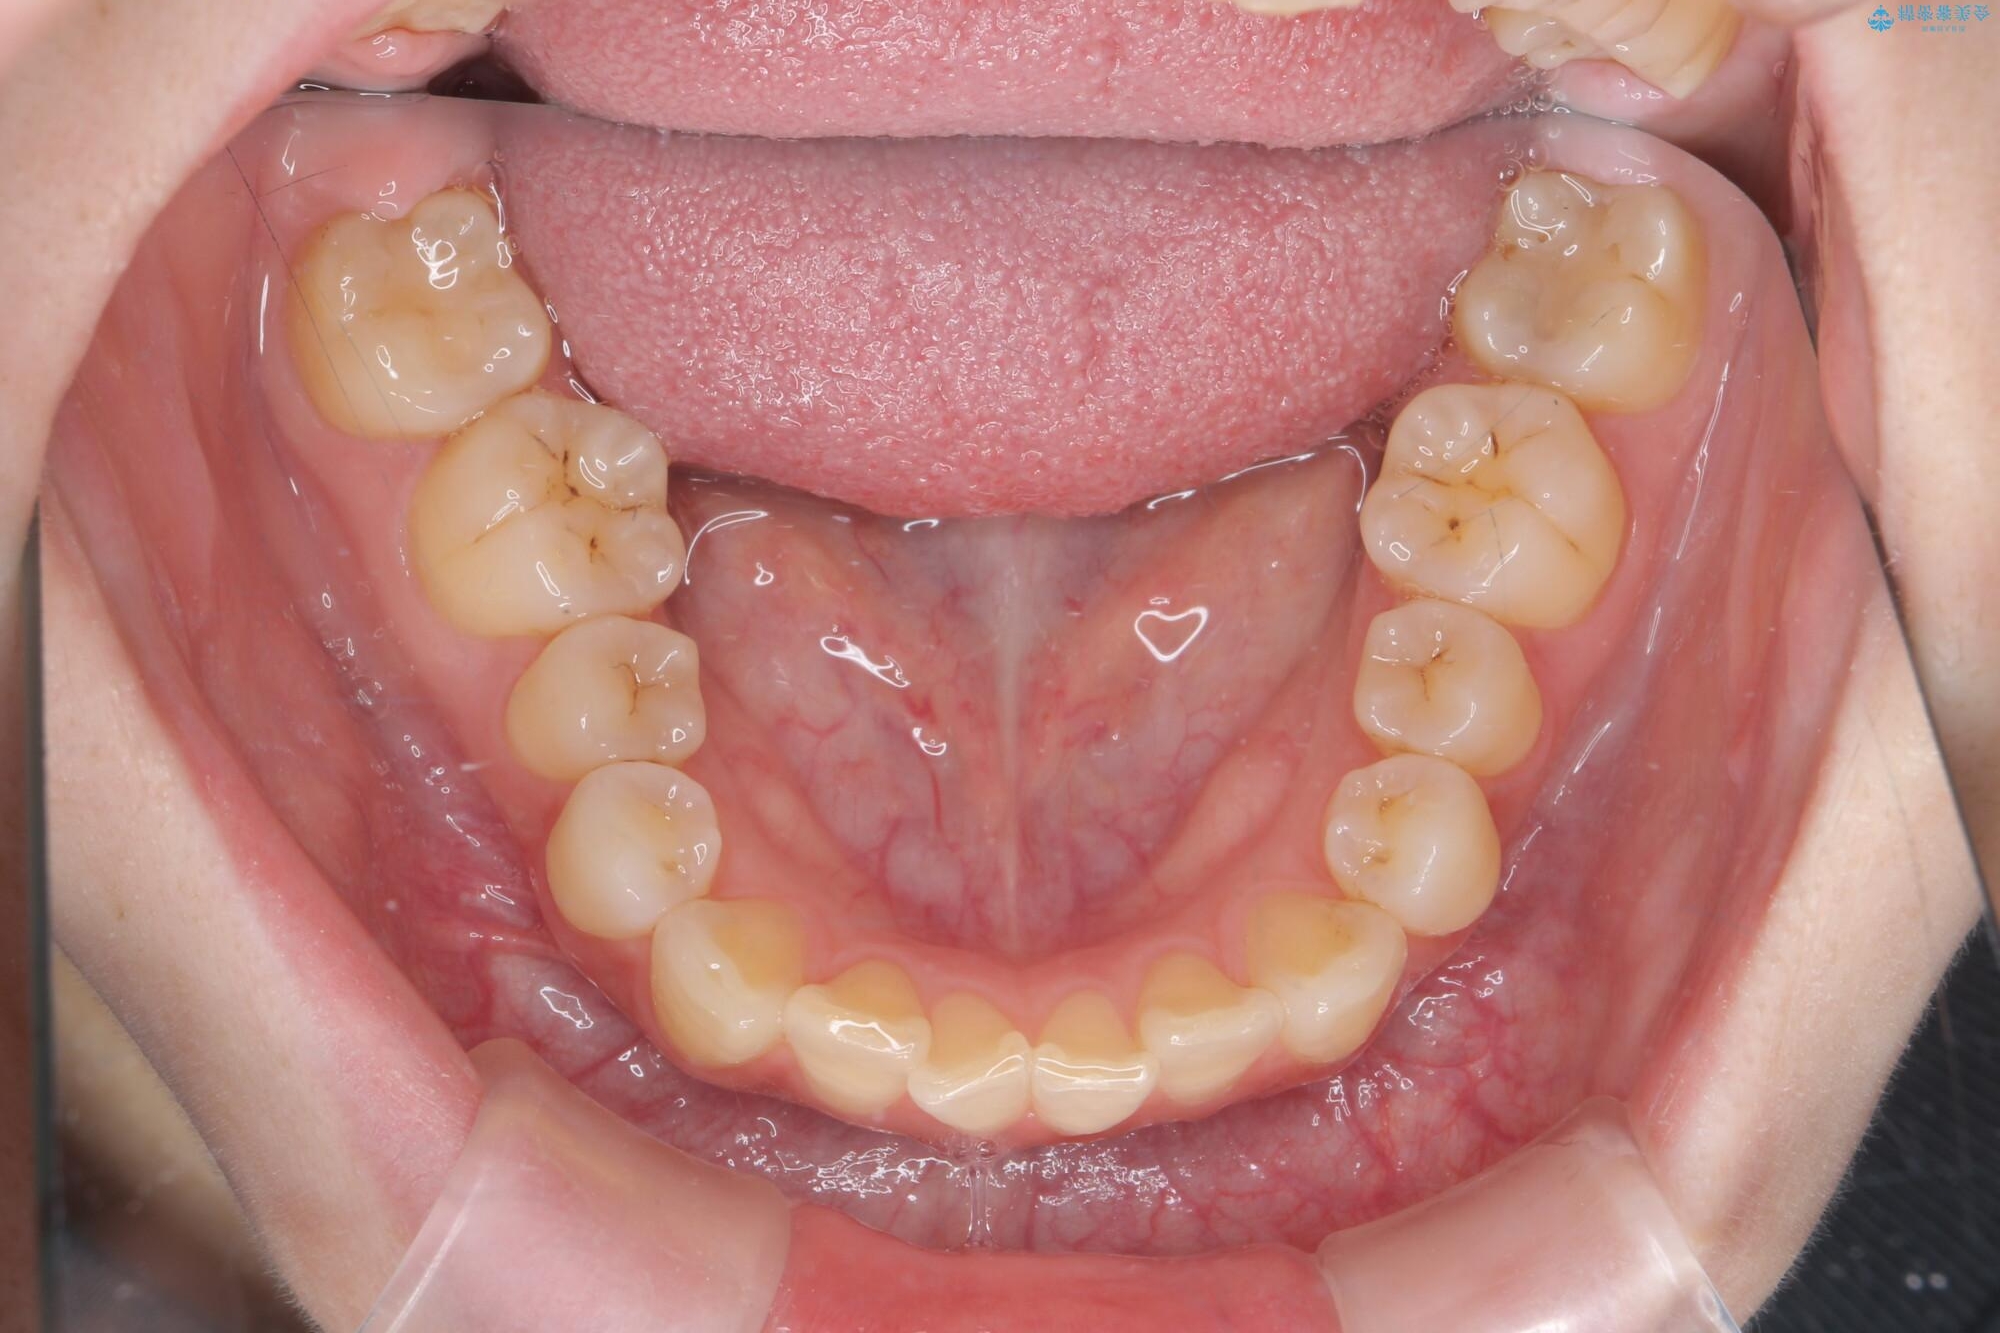

治療前

傾いた前歯、インビザラインで改善 治療前画像 傾いた前歯、インビザラインで改善 治療前画像 傾いた前歯、インビザラインで改善 治療前画像 傾いた前歯、インビザラインで改善 治療前画像